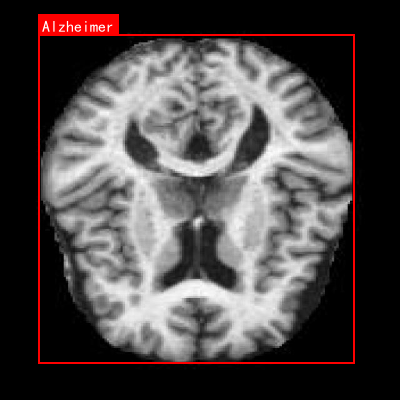

图1:不同神经退行性疾病的MRI影像特征对比,从左到右分别为健康对照组、阿尔茨海默病和帕金森病患者

本数据集名为Enfermedades_cerebro,版本为v1,创建于2024年6月14日,是一个专注于神经退行性疾病诊断的医学影像数据集。该数据集通过qunshankj平台构建,采用CC BY 4.0许可协议进行授权,共包含999张脑部横断面磁共振成像(MRI)图像,所有图像均以YOLOv8格式进行了标注。数据集涵盖了三个主要类别:阿尔茨海默病(Alzheimer)、健康对照组(CONTROL)以及帕金森病(parkinson),为神经退行性疾病的计算机辅助诊断提供了宝贵的训练资源。在预处理阶段,所有图像均经过了自动方向校正(EXIF方向信息被剥离)并统一调整为640×640像素尺寸,但未应用任何图像增强技术。数据集按照标准划分方式组织为训练集、验证集和测试集三个子集,为模型开发与评估提供了完整的数据支持。从影像学特征来看,数据集中的MRI图像清晰展示了大脑的解剖结构,包括灰质与白质的对比、脑沟回形态、侧脑室大小等关键指标,这些特征对于区分不同类型的神经退行性疾病具有重要价值。特别是阿尔茨海默病的图像,呈现出典型的脑萎缩表现,如侧脑室扩大、脑沟增宽、脑回变薄等病理特征,为算法学习提供了直观的视觉依据。该数据集的开发与应用,有望提高神经退行性疾病的早期诊断准确性,辅助临床医生进行更高效的疾病筛查与评估。